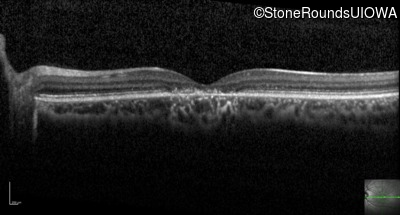

Optical Coherence Tomography - Right - 20/125 -2

Exemplar / OCT Stack

OCT Stack